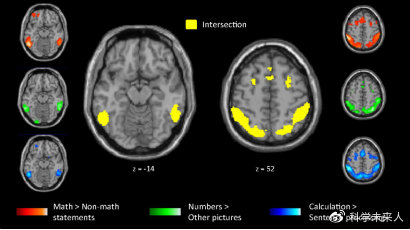

2016年,法国巴黎-萨克雷大学的研究人员发现,当被试者大脑在处理高等数学命题(如拓扑学或几何学)时,那些数学好的人被激活的是3块边缘系统脑区,它们是双侧顶内沟区域(IPS)、双侧颞下回区域(IT)、前额叶皮层区域;而数学不好的人(他们在非数学领域同样成就非凡)被激活的,主要是语言功能脑区[2]。

数学相关脑区:绿色是阿拉伯数字概念相关脑区,蓝色是数字运算相关脑区,红色是听到高等数学命题时的“数学家相关脑区”,它与前两者高度重叠(黄色区域)。图片来源:参考文献[2]。

这意思就是,数学好的人真的是在用专门脑区处理数学问题,而其他领域的人纵然同样是精英(如大作家维克多·雨果),也只是像听天书一样在听题看题。只不过与普通人相比,天才或经过训练的数学家很擅长在处理高等数学命题时调用“数学脑区”,而文学家却可能语义处理的脑区更发达,对数字等反倒不敏感了[2]。所以,孩子为什么在该用加法的地方错用了减法?很可能就是题干中的“还剩几个”误导了他。这是很多成年人做数学题的困扰吧:很容易在题干中钻牛角眼,为此痛苦不堪~~